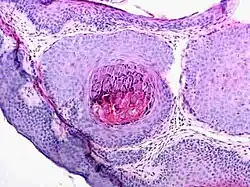

Dank des charakteristischen Aussehens ist meist eine Blickdiagnose möglich. In Zweifelsfällen kann eine histopathologische Untersuchung die Diagnose sichern.

Dellwarzen sind im Durchschnitt 2–6 mm große, weiße, rötliche oder hautfarbene Knötchen mit glatter und oft glänzender Oberfläche, die stets multipel auftreten. Sie haben meist in der Mitte eine Delle, die eine kleine Öffnung aufweisen kann, und treten in unterschiedlicher Anzahl (wenige bis mehrere Hundert Mollusken) am ganzen Körper auf, besonders an Armen, Händen, Fingern, Genitalien und Oberkörper. Beim Erwachsenen ist die Verbreitung im Genitalbereich vorherrschend. Druck auf Dellwarzen führt zur Entleerung einer rahmartigen bis teigigen Masse, die auch Molluscumbrei oder Molluscumkörperchen genannt wird. Dellwarzen kommen besonders häufig bei Kindern vor, insbesondere bei Kindern mit atopischem Ekzem (Neurodermitis), bei Personen mit Immunschwäche, Personen unter Kortisontherapie und sexuell aktiven Erwachsenen.